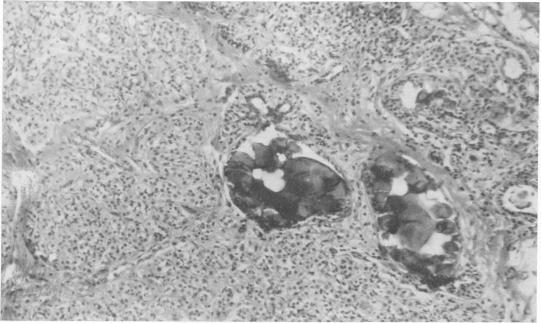

Management of nonpalpable breast carcinoma discovered by mammography.

Ann Surg. 1969 Sep;170(3):385-95. doi: 10.1097/00000658-196909010-00007.